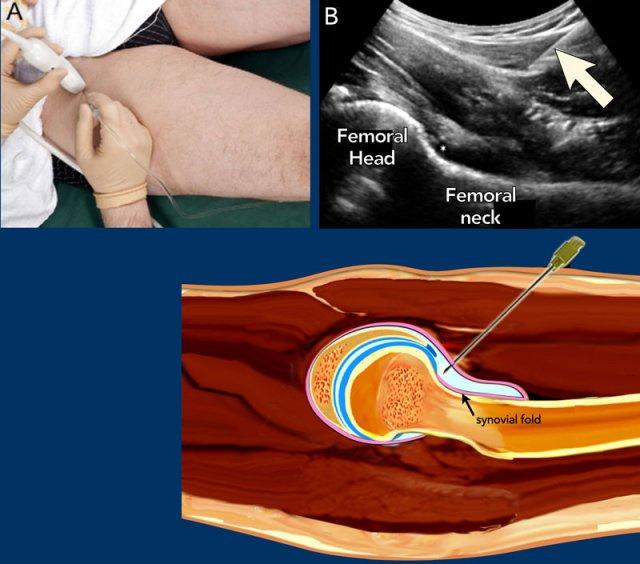

Hip

Bệnh nhân được đặt ở tư thế nằm ngửa. Chân được giữ ở tư thế xoay trong nhẹ và dạng ra, giúp giảm căng thẳng lên các cấu trúc bao khớp và di chuyển gân cơ thắt lưng chậu cùng túi thanh dịch về phía trong ra khỏi đường đi dự kiến của kim.

Ưu tiên sử dụng đầu dò mảng cong 5-3,5 MHz, cung cấp độ sâu thâm nhập cần thiết.

Thông thường, kim cỡ 21 gauge với chiều dài 9 cm được sử dụng cho người lớn trung bình. Ở người lớn nhỏ hơn hoặc trẻ em, có thể sử dụng kim tiêm dưới da cỡ 23 gauge, dài 5 cm.

Thuốc gây tê cục bộ có thể được tiêm trước khi tiêm chính, tuy nhiên điều này đòi hỏi thao tác thêm cũng như đưa dịch không cản quang (thuốc gây tê) vào khớp, làm giảm không gian cho chất cản quang trong khoang khớp vốn đã hạn chế, đồng thời có thể cần đến 2 lần chọc kim.

Kim tiêm có thể vô tình bị rút ra khỏi khớp sau khi tiêm thuốc gây tê trong quá trình chuyển đổi để kết nối bơm tiêm với chất cản quang. Điều này có thể tránh được bằng cách sử dụng đầu nối ba chiều giữa hai bơm tiêm chứa thuốc gây tê và dịch tiêm (chất cản quang hoặc thuốc).

Kim tiêm được đưa vào theo góc từ đuôi đến đầu dọc theo trục dài của đầu dò, hướng đến túi cùng trước gần chỗ nối cổ xương đùi với chỏm xương đùi (xem siêu âm và hình minh họa).

Vát của kim nên hướng về phía khớp.

Khi kim tiếp xúc với chỗ nối đầu-cổ xương đùi, kim được rút lui nhẹ để tránh vô tình tiêm vào bên dưới nếp gấp bao hoạt dịch của bao khớp háng (xem hình vẽ).

Nếu được định vị chính xác trong bao khớp, 10-15 mL thuốc cản quang hoặc thuốc điều trị được tiêm vào và túi cùng phía trước sẽ căng phồng do dịch tiêm vào, xác nhận vị trí trong khớp.